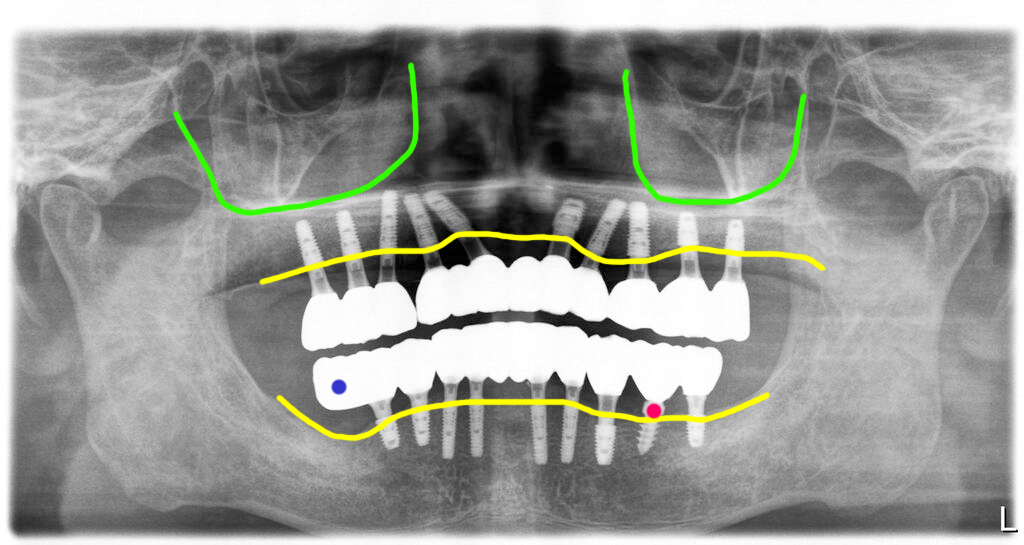

상악은 임플란트주위염으로 뼈가 녹은 임플란트 4개를 제거한 후 남아있는 뼈에 10개의 임플란트를 식립했습니다.

하악 우측 어금니 부위는 염증이 심할 뿐 아니라 신경관과의 거리가 너무 가까워 그부분은 식립을 하지 않았어요. 임플란트를 심지 않은 부분은 캔틸레버로 처리했어요. 하악좌측에 이전에 심은 임플란트 중 한개는 상태가 괜찮아 남겼구요.

전체적으로 낮아진 고경도 정상적으로 맞추어 주어 환자의 얼굴도 훨씬 좋아보이게 했습니다.

총 4회 방문 치료기간 6개월 전체임플란트 치료완료

이렇게 해서 이 환자는 총 4회 방문 총 치료기간 6개월에 이전에 심은 임플란트는 제거하고 새로 전체임플란트를 완료해 드렸습니다.

수술 당일부터 바로 임시치아를 예쁘게 적용해 드려서 치아 없이 지내지 않게 해 드렸구요. 임플란트가 완전히 고정이 될 때까지는 유동식을 하셨습니다. 현재까지 환자는 잘 관리 중이며 정기검진도 잘 받고 계십니다.